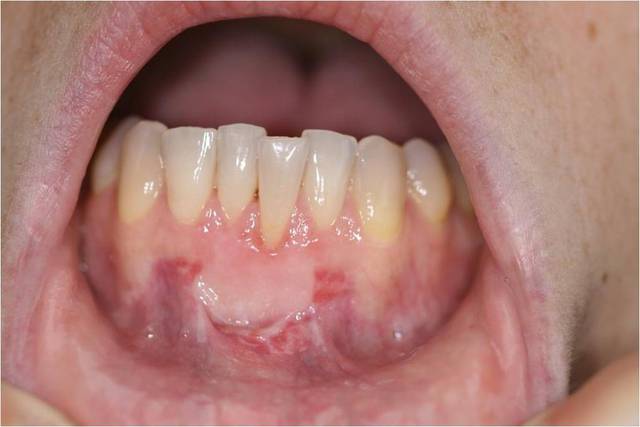

salut cousin... présentement tu vas arriver au même résultat qu'une greffe épithéliale libre standard de 1.25mm d'étaisseur avec plus de domage au niveau des papilles étant donné le greffon trop apicale et le tout était bien préparé au niveau du lit receveur... suture suspendue...

en post-op tu va probablement avoir créer un déhiscence au mb de la dent 32...

Si l'ambition est de couvrir l'integralite de la recession avec une seule intervention, j'aurais étendu la greffe à 2 dents ce qui aurait permis d'accroitre le lit receveur en augmentant par cela la surface de vascularisation et l'immobilisation du greffon.

Une autre différence est que j'aurais utilisé des techniques microchirurgicales qui permettent d'obtenir des incisions propres, une manipulation tissulaire délicate et une mise en place de sutures plus précise.

Enfin, les points utilisés auraient été différents : double crossed, points papillaires, périphériques et de plaquage.

Le cas de Tillc n'est cependant pas perdu mais il lui sera certainement nécessaire de réintervenir avec un lambeau tracté coronairement pour améliorer le recouvrement radiculaire